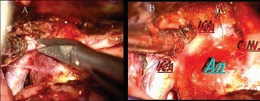

床突旁动脉瘤朝上型通常在手术过程中相较其他床突旁动脉瘤更为简单,因为其整个动脉瘤颈均位于硬膜内部,这为手术操作提供了便利。然而,对于一些大型、巨型或较小的动脉瘤,其近端颈部可能被前床突覆盖,此时必须磨除床突以充分暴露近端颈部,并确定眼动脉的起源位置(如图2C-2F所示)。同时,暴露颈内动脉近端至远端硬膜环的床突段有助于观察整个瘤颈区域,特别是在处理巨大动脉瘤的病例时(如图3所示)。

更值得注意的是,对床突的磨除可以有效地切除远端硬膜环,并清理颈动脉床突段上的各层组织,以确保在夹闭后不会出现滑脱或颈动脉狭窄的情况。

在处理颈内动脉时,我们始终认为,通过血管内或直接颈部暴露来进行近端控制是有必要的。然而,为了更好地完成夹闭过程,我们仍需磨除前床突,以便观察颈内动脉近端至远端硬膜环的情况。